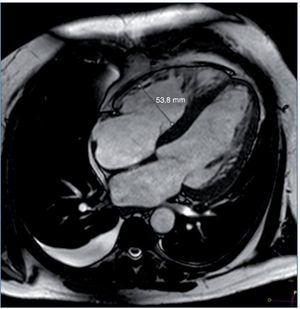

Entre las pruebas complementarias destacaba un ecocardiograma en el que se objetivó una dilatación y una hipertrofia biventricular grave, con una disfunción sistólica grave de ambos ventrículos, una disfunción diastólica tipo III y una insuficiencia mitral funcional moderada (fig. 1). Ante estos hallazgos se realizó coronariografía, que descartó lesiones coronarias. En el mismo procedimiento se visualizaron las arterias renales, que no mostraron datos de estenosis. Durante el ingreso, el paciente presentó un episodio de amaurosis fugax, por lo que se realizaron una TC y una RM cerebrales, que mostraron enfermedad isquémica de pequeño vaso (fig. 2).

Figura 1. Resonancia magnética cardíaca del caso clínico 2. Ventrículo izquierdo gravemente dilatado e hipertrófico, FEVI 41%. Ventrículo derecho moderadamente dilatado, FEVD 39%.